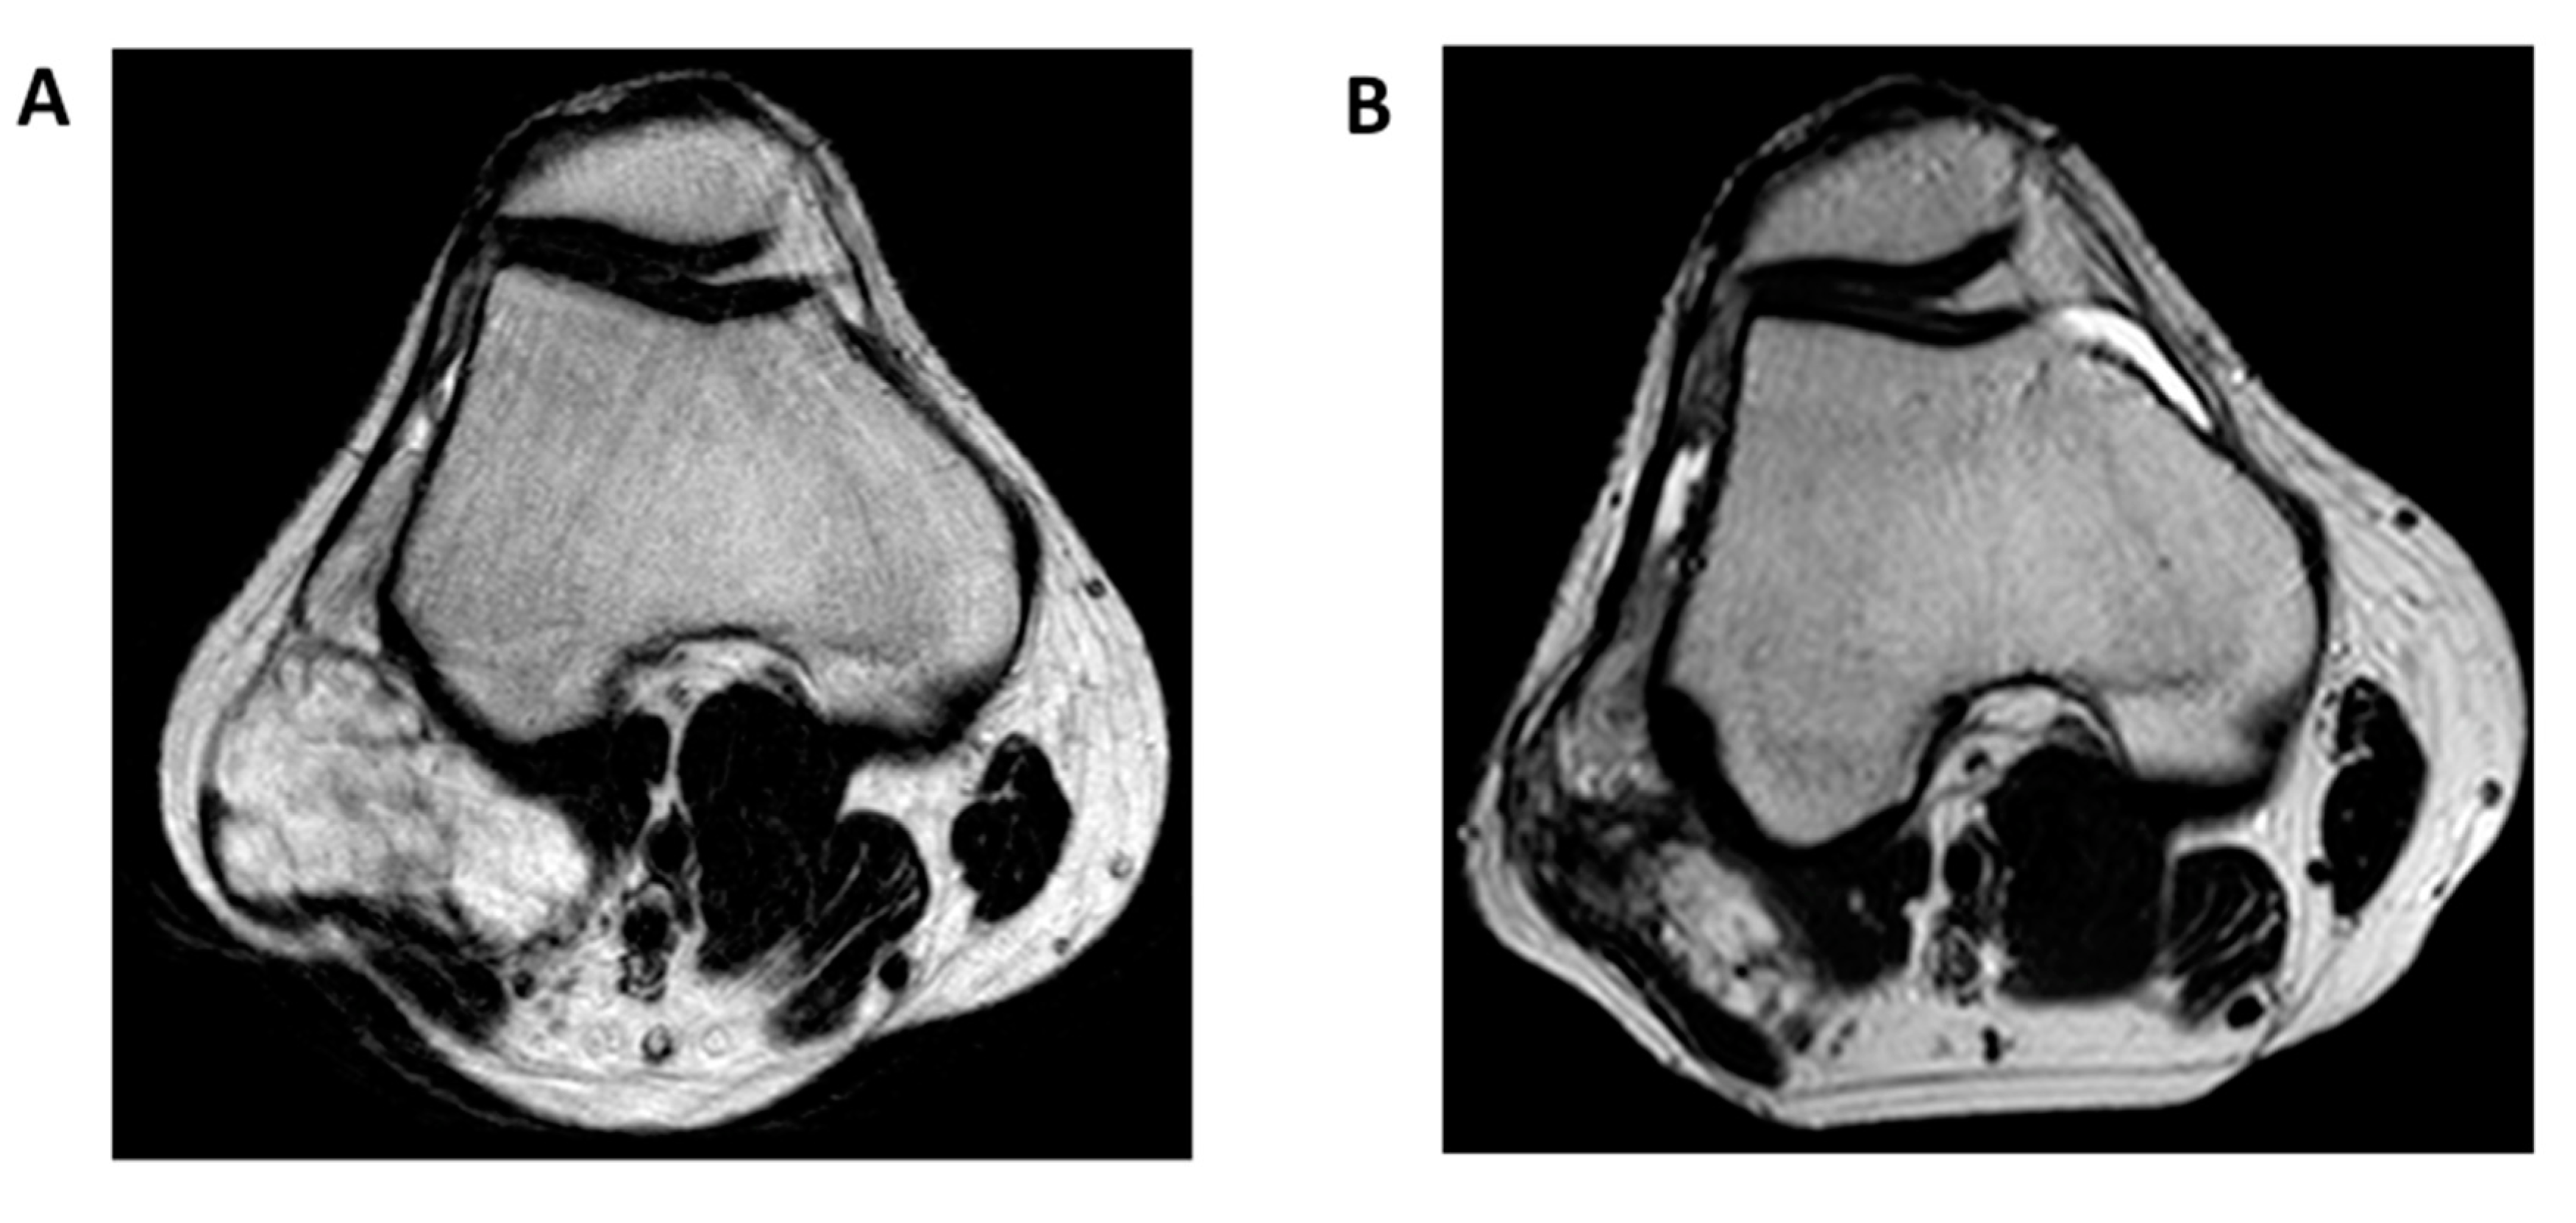

- Murphey, M.D.; Walker, E.A.; Wilson, A.J.; Kransdorf, M.J.; Temple, H.T.; Gannon, F.H. From the archives of the AFIP: Imaging of primary chondrosarcoma: Radiologic-pathologic correlation. Radiographics 2003, 23, 1245–1278. [Google Scholar] [CrossRef]

- Kapoor, N.; Shinagare, A.B.; Jagannathan, J.P.; Shah, S.H.; Krajewski, K.M.; Hornick, J.L.; Ramaiya, N.H. Clinical and radiologic features of extraskeletal myxoid chondrosarcoma including initial presentation, local recurrence and metastases. Radiol. Oncol. 2014, 48, 235–242. [Google Scholar] [CrossRef] [PubMed]

- Tateishi, U.; Hasegawa, T.; Nojima, T.; Takegami, T.; Arai, Y. MRI features of extraskeletal myxoid chondrosarcoma. Skelet. Radiol. 2006, 35, 27–33. [Google Scholar] [CrossRef] [PubMed]